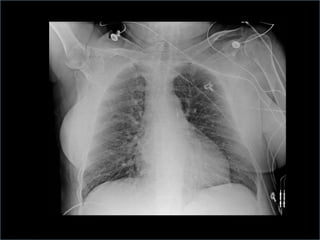

 Chest x-ray or fluoroscopy

radiopaque tip lies in the 2nd intercostal spaces

just above the left main bronchus; lower end of